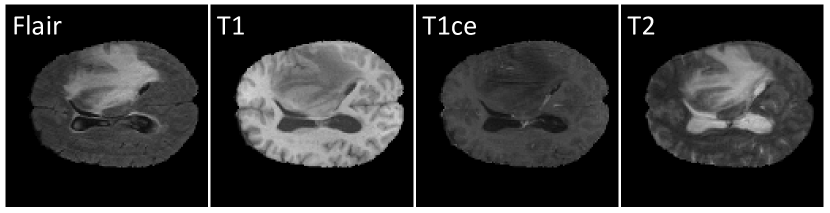

Multi-modal brain images from MRI (Magnetic Resonance Imaging) scans are widely used in various clinical scenarios[1, 2]. These images are further divided into several modalities(sequences), such as T1-weighted (T1), T1-with-contrast-enhanced (T1ce), T2-weighted (T2), T2-fluid-attenuated inversion recovery (Flair), etc. Each modality exhibits distinct contrasts, providing complementary lesion information from different perspectives. As shown in Figure 1, Flair and T2 images depict the peritumoral edema areas clearly, while T1 images highlight the white and gray matter tissues[3], making them suitable for presenting anatomical structures. T1ce images delineate the structures and the edges of the tumors[4], which is convenient to observe the morphology of different types of tumors. Fully paired multi-modal images assist doctors in achieving more precise diagnoses[5].

Refer to caption

Figure 1: Examples of brain tumor MRI images from different modalities.